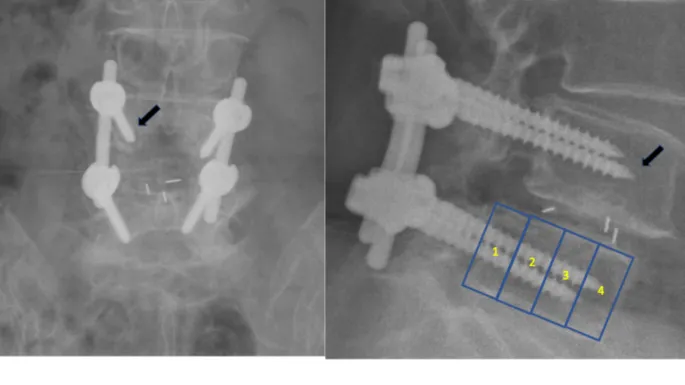

⭐ A "radiolucent line" >2 mm wide at the bone-cement or bone-implant interface on X-ray is a key sign of loosening.